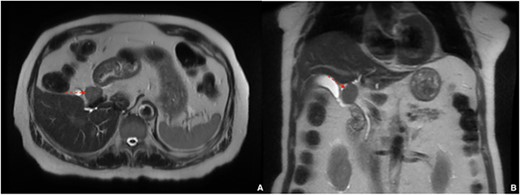

A 77-year-old male with a history of hypertension and hypothyroidism underwent imaging for possible fatty liver disease and was found to have a 3 cm porta hepatis mass causing mild intrahepatic biliary ductal dilation on Magnetic Resonance Elastography (Fig. 1). A multi-phase computed tomography (CT) obtained and showed an isolated 2.8 cm hyperenhancing nodular mass in the liver hilum (Fig. 2). The patient did not have any symptoms, such as jaundice, vomiting, flushing or diarrhea. Physical examination and all biochemical markers were normal, including liver function tests and serum tumor markers (alpha-fetoprotein and carcinoembryonic antigen 19–9). No serologic evidence of hepatitis B or C virus infection was found.

A multi-phase CT showing a 2.8 cm hyperenhancing nodular mass in the liver hilum; (A) axial view, (B) coronal view.